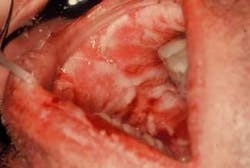

The oral lesions (Figure 2) have an aphthous-like appearance and are superficially distributed throughout the oral tissues. He also reports pain and a slight fever. His lymph nodes are indurated, mobile, and tender when palpated (lymphadenopathy).

Clinical impressions: The skin lesions in erythema multiforme present as erythematous papules, which enlarge to form central vesicles, or bullae, creating what is referred to as “iris,” “target,” or “bull’s eye” lesions. Target lesions usually appear on skin surfaces and the oral lesions usually have an ulcerative type appearance. The lips, buccal mucosa, palate, and tongue are the sites most frequently affected. Depending upon the severity of the condition, the patient may have both skin and oral lesions.

Oral and perioral features: The skin may have a central, dark-red zone bordered by a blanched halo with an erythematous zone at the periphery. When vesicles and bullae are present both with cutaneous and oral lesions, the course of the disorder is considered more severe. Oral lesions are reported in a range of approximately 50 percent of cases. Sometimes lesions are confined just to the oral tissues. The disease is termed minor and major erythema multiforme.